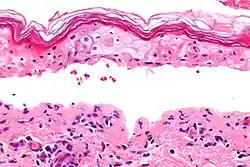

Definitive diagnosis of TEN often requires biopsy confirmation. Histologically, early TEN shows scattered necrotic keratinocytes. In more advanced TEN, full thickness epidermal necrosis is visualized, with a subepidermal split, and scant inflammatory infiltrate in the papillary dermis. Epidermal necrosis found on histology is a sensitive but nonspecific finding for TEN.[7]

Confluent Epidermal Necrosis, low mag

Confluent Epidermal Necrosis, high mag